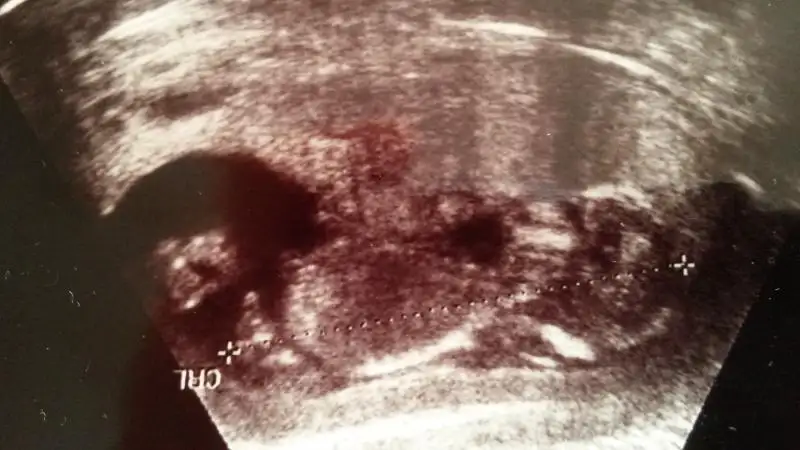

canım bu görüntüsü daha yeni sayılır 13+2 günlükken daha net sanki bakabilirmisin